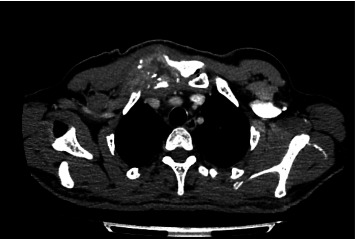

IgG4-related disease (IgG4-RD) is a rare, progressive, and immune-mediated fibroinflammatory disorder that primarily affects middle-aged men and is more prevalent in Asian populations. Although extensively studied, its pathophysiology remains incompletely understood. This case report describes a 44-year-old male presenting with multiple abscesses and progressive inflammatory symptoms, ultimately diagnosed with IgG4-RD with musculoskeletal involvement. Imaging and histopathological evaluation confirmed osteolytic lesions and significant IgG4-positive plasma cell infiltration. Soft tissue tumors in IgG4-RD are exceptionally rare, further emphasizing the uniqueness of this case. The patient showed clinical improvement with corticosteroid therapy. This case highlights the importance of considering IgG4-RD in the differential diagnosis of soft tissue and bone lesions and underscores the need for a multidisciplinary diagnostic approach.